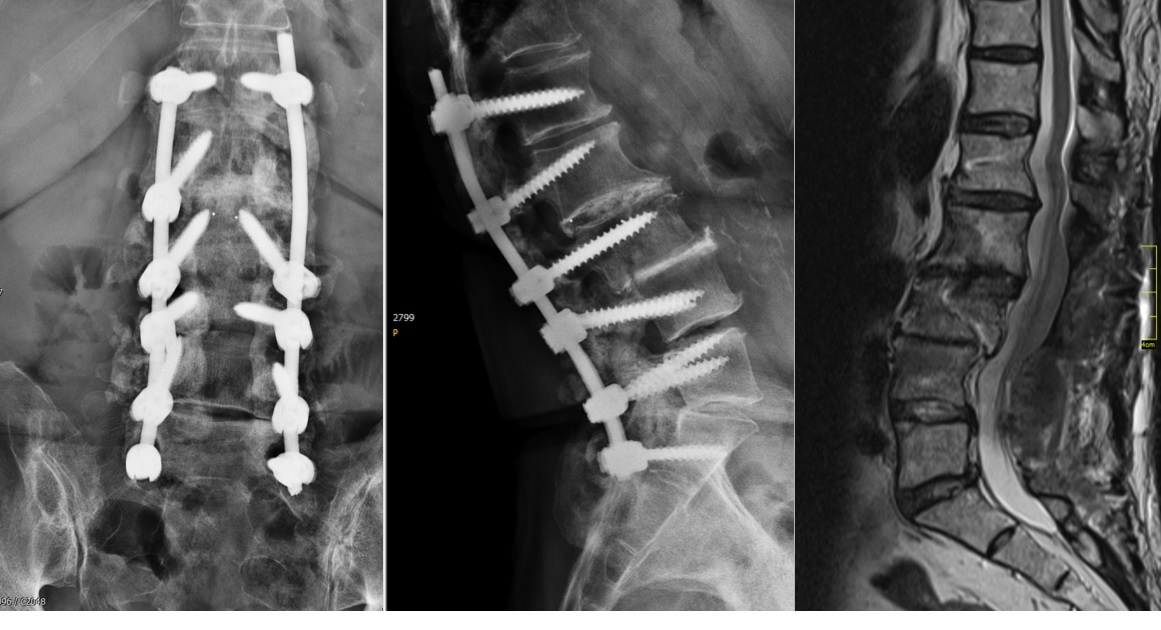

A CT scan allowed a more detailed assessment (Fig 7). There was an obvious nonunion at L5/S1, with loose screws in the sacrum (red circle). Furthermore, there was instability at L4/L5 as the intervertebral disc presented with an important vacuum phenomenon (asterisk). Foraminal stenosis at L5/S1 (not shown) seemed to be the reason behind the persistent leg pain.

The treatment plan was an anterior height restoration and fusion of L5/S1 and L4/L5. A posterior revision surgery was not considered due to the wide decompression and obvious scar formation. For the correction of level L4/L5, an oblique anterolateral approach (OLIF) was selected due to considerable calcification of the aorta and the iliac vessels. At the L5/S1 level, a straight anterior approach was selected and an additional plate fixation (ATB) was performed.

At level L5/S1, a large cage with an angulation of 14 was selected and for L4/L5, a large cage with an angulation of 10 was placed. In order to perform a fusion, the cages were each filled with 6 mg of BMPII.

From six months postoperatively, leg discomfort decreased. Within an additional four months, pain disappeared completely and both foot and hip weakness recovered. The back pain persists to a certain extent but is not impedingthe patient in her daily activities. The x-ray taken 10 months after the anterior revision surgery revealed a complete and solid fusion on both levels (Fig 8). This is confirmed by the appearance of dense bone in the radiolucentcage.